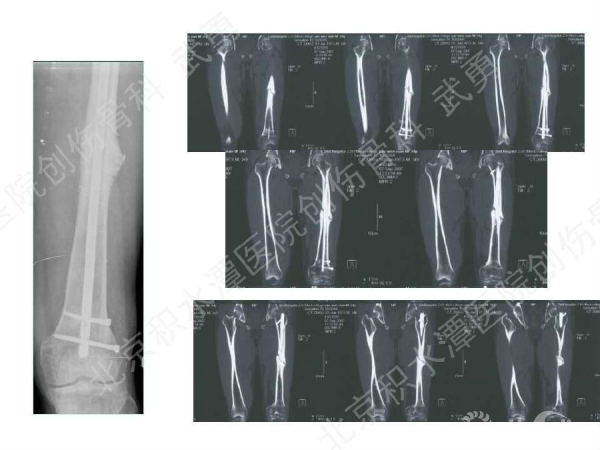

髓内钉骨不连的类型:增生型、萎缩型

病例分析:

主要发生在干骺端, 髓腔增宽,无法控制稳定(成角)

解决办法:阻挡钉技术(Poller screw)等